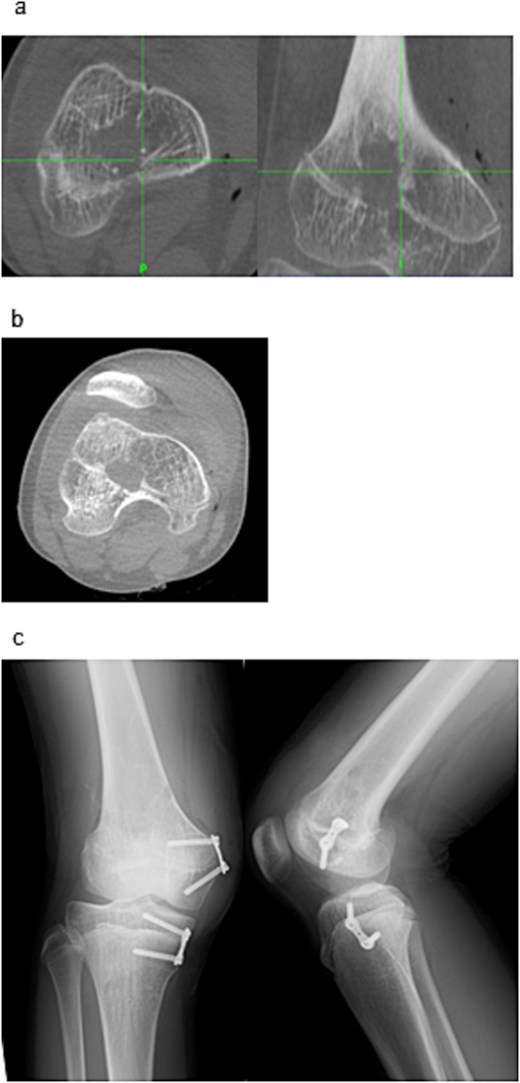

Surgery was performed under general anesthesia with the patient supine. Two 3 mm reference pins were inserted into the femoral diaphysis to secure the Stealth Station™ navigation tracker (Fig. 2a). Intraoperative CT using the O-arm™ system integrated with the navigation platform was used to identify the physeal bar’s location and orientation (Fig. 2b–d).

Intraoperative setup and portal creation. (a) Two 3-mm pins were inserted into the femoral diaphysis to secure the tracker of the Stealth Station™ system. (b) Intraoperative CT was performed using the O-arm™ system and integrated with the navigation system. (c) The location and trajectory to the physeal bar were identified using navigation. (d) Two 1.6-mm Kirschner wires were inserted from the medial and lateral aspects toward the physeal bar under fluoroscopic guidance. (e) Drill portals (8 mm) were created along the wire tracts. (f) A 4-mm arthroscope was inserted through one portal for endoscopic visualization.

Two 1.6 mm Kirschner wires were inserted percutaneously from the medial and lateral distal femoral sides toward the bar (Fig. 2e), and 8 mm drill portals were created along the wires (Fig. 2f). A 4 mm arthroscope (Stryker Corporation, Kalamazoo, MI, USA) was introduced through one portal for direct visualization of the physeal bar (Fig. 2g). A Stealth-Midas™ high-speed drill (Medtronic) was advanced through the contralateral portal. Resection was performed under concurrent navigational and endoscopic monitoring (Fig. 3a and b). Complete bar removal was confirmed visually and on the navigational display (Fig. 3c). Intraoperative CT via O-arm confirmed a thorough excision (Fig. 4a) with no cortical perforation (Fig. 4b).